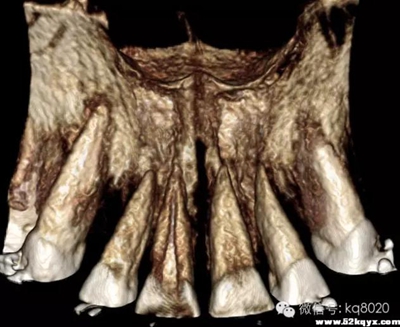

顴牙槽嵴(成人多在67之間,未成年多在56之間或6上方,根據(jù)CT確定)

危險因素:此處植入容易穿破上頜竇底,植入角度需注意;骨質(zhì)較為堅(jiān)硬,支抗釘易折斷

植入位置和角度:在不滑脫的基礎(chǔ)上越平行于骨面越安全。要根據(jù)顴牙槽嵴的斜度決定植入角度,為避免滑脫,

可先垂直于骨面植入,在調(diào)整方向斜向上,一般植入角度向牙合面旋轉(zhuǎn)60°-70°

大?。河捎诖颂幑琴|(zhì)堅(jiān)硬,宜用10×2.0mm,且支抗釘尖端應(yīng)有切削頭設(shè)計(jì),以切削骨碎屑,利于植入腭側(cè)牙根之間